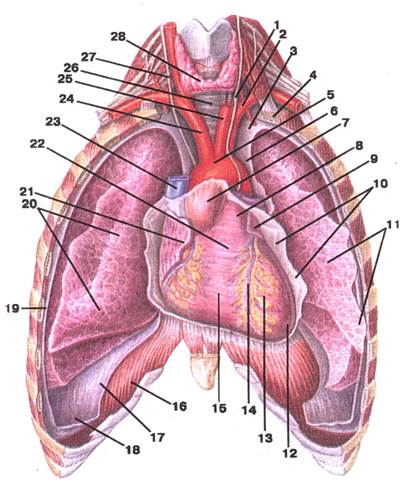

Малюнок А. 8 – Положення серця. Вигляд спереду:

1 -n. vagus sinister; 2 -а. subclavia sinistra; 3 -cupula pleurae; 4 -costa I; 5 -arcus aortae; 6 -pars mediastinalis (pleura parietalis); 7 -aorta ascendcns; 8 -truncus pulmonalis; 9 -auricula sinistra (cordis); 10 -pericardium; 11 ‑pulmo sinister; 12 -apex cordis; 13 -ventriculus sinister; 14 -sulcus intervcntricularis anterior; 15 -ventriculus dexter; 16 -diaphragma; 17 -pars diaphragmatica (pleura parietalis); 18 -recessus costodiaphragmaticus; 19 -pars costalis (pleura parietalis); 20 -pulmo dexter; 21 ‑auricula dextra (cordis); 22 -conus arteriosus; 23 -v. cava superior; 24 -truneus brachiocephalicus; 25 -a. carotis communis sinistra; 26 -trachea; 27 -n. vagus dexter; 28 -glandula thyroidea